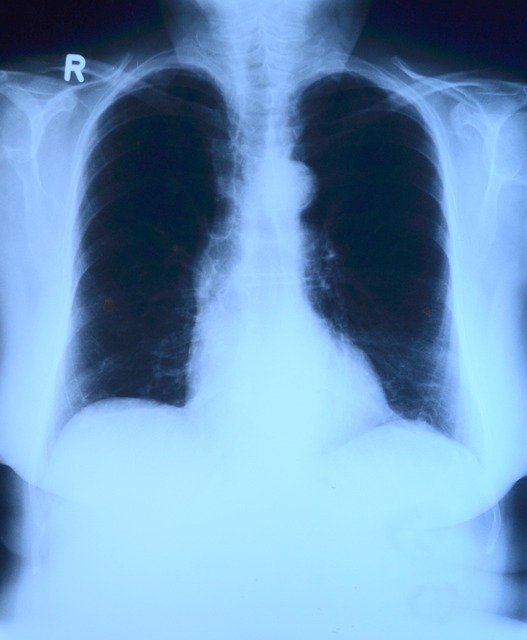

폐렴은 전 세계 수백만 명의 사람들에게 영향을 미치는 흔하고 잠재적으로 심각한 호흡기 감염입니다. 폐렴은 모든 시기의 개인에게 영향을 미칠 수 있지만, 특히 어린아이들, 나이 든 어른들, 그리고 취약한 시스템을 가진 사람들에게 위험합니다. 이번 폐렴에 대한 블로그 게시물에서는 폐렴의 원인, 증상, 치료 방법, 사전 예방 전략 등을 살펴보고 호흡기 건강을 지킬 수 있는 소중한 자료와 정보를 제공할 예정입니다.

폐렴의 증상은 감염의 종류와 개인의 전반적인 건강에 따라 달라질 수 있습니다. 그러나 다음과 같은 일반적인 징후와 증상이 있습니다. 기침 및 가래, 발열, 호흡 곤란, 기침이나 심호흡으로 악화되는 흉통, 피로 또는 몸 상태가 전반적으로 좋지 않음, 빠른 호흡 또는 심박수 증가, 입술이나 손톱에 푸르스름한 색조. 심한 경우 산소 부족이 발생할 수 있습니다. 폐렴은 합병증을 예방하기 위해 신속한 치료와 치료가 필요합니다. 치료는 감염의 유형과 심각성, 그리고 개인 건강 상태 등에 따라 달라집니다. 반드시 전문 의사와 상담하시고 적절한 치료를 받으시는걸 권장합니다.